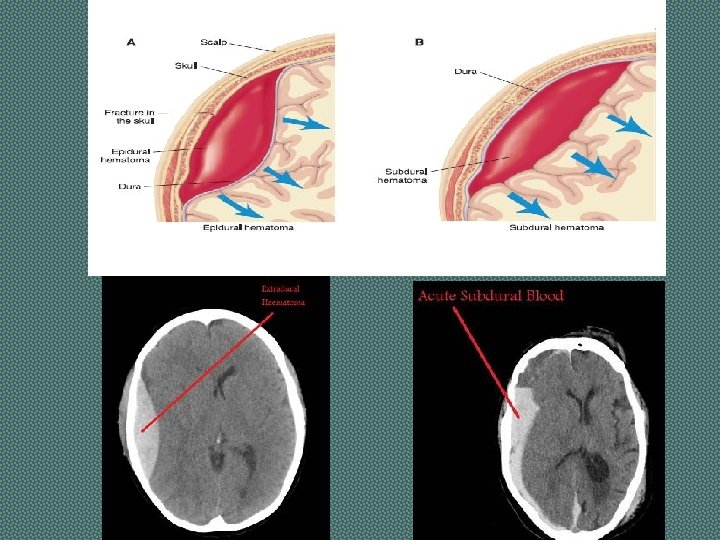

SPACE OCCUPYING LESION Lesion which occupy the cranial cavity and displace or destroy existing structures Causes: Tumour, Abscess, Hematoma, Tuberculomas Symptoms: H/O gradual onset of weakness developing over weeks to months. Headache and vomiting There may be H/O trauma (Hematoma) H/O waxing and waning of concious level (Subdural Hematoma) H/O fever and ear discharge suggest an abscess. Signs: In addition to motor deficit, following signs may be present: Bradycardia Fundoscopy……Papilledema Investigations: CT scan (with contrast), MRI

Investigations - STROKE • Imaging in Acute Stroke. • Non-contrast CT: will demonstrate haemorrhage immediately but cerebral infarction is often not detected or only subtle changes are seen initially.